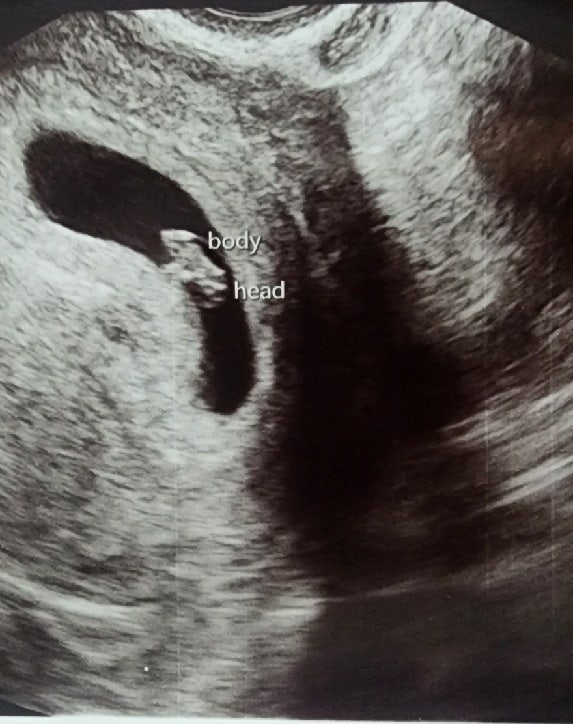

[pregnancy.6]엄마와 인연이 생기는 임신 9주 10주 이야기(임신초기검사,젤리곰초음파,차량벚꽃구경,애플망고,달서구보건소 기형아검사쿠폰,보건소철분제,올드페리도넛,달사진)

안녕하세요~ 저는 이제 임신 9주와 10주 차를 맞이했어요 임신 9주와 10주엔 사실 눕눕이었어요..... 출혈...